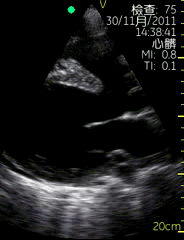

心尖四腔切面

| 图像名称: | 心尖四腔切面(彩色) |

| 心尖四腔切面(彩色) | | 介绍重点: | 房室瓣彩色多普勒显示有心房到心室的单向红色血流 |

| 房室瓣口彩色多普勒显示收缩期有心室到心房的反向蓝色血流 | | 临床用途: | 瓣膜功能正常 |

| 二尖瓣关闭不全,三尖瓣关闭不全 |